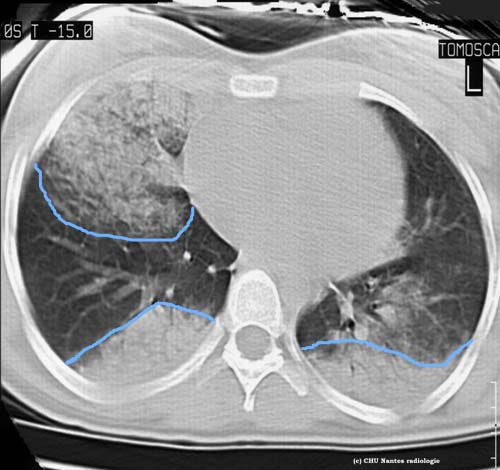

Syndrome alvéolaire

coupe TDM en fenêtre parenchymateuse

Opacités aux limites floues avec bronchogramme aérien ( visualisation des clartés bronchiques ) du territoire lobaire moyen droit et des régions déclives des lobes inférieurs: contusions pulmonaires dans le cadre d'un polytraumatisme